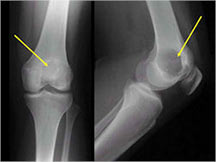

Radiographic imaging is used to help form a diagnosis. These include X-Ray, MRI, CT and Bone Scans.

An example of an X-ray is shown.